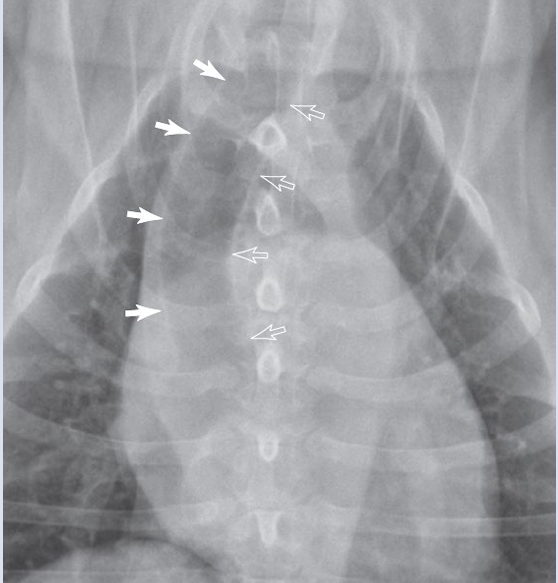

DV

Expiration

inspiration

arrow pointed the THYMUS

dark white: right margin of trachea

light white arrow: left margin of trachea